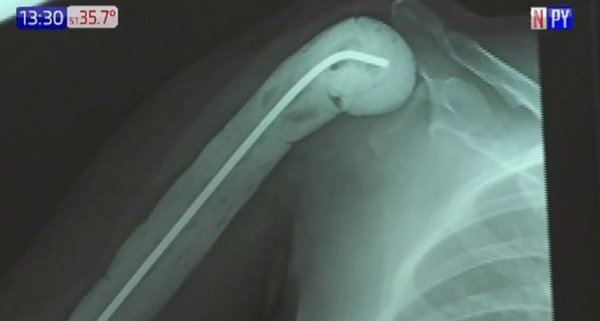

Gracias a la donación del tejido de un paciente cadavérico, doctores del Hospital de Clínicas subsanaron un tumor óseo de una adolescente. ...[Leer más]